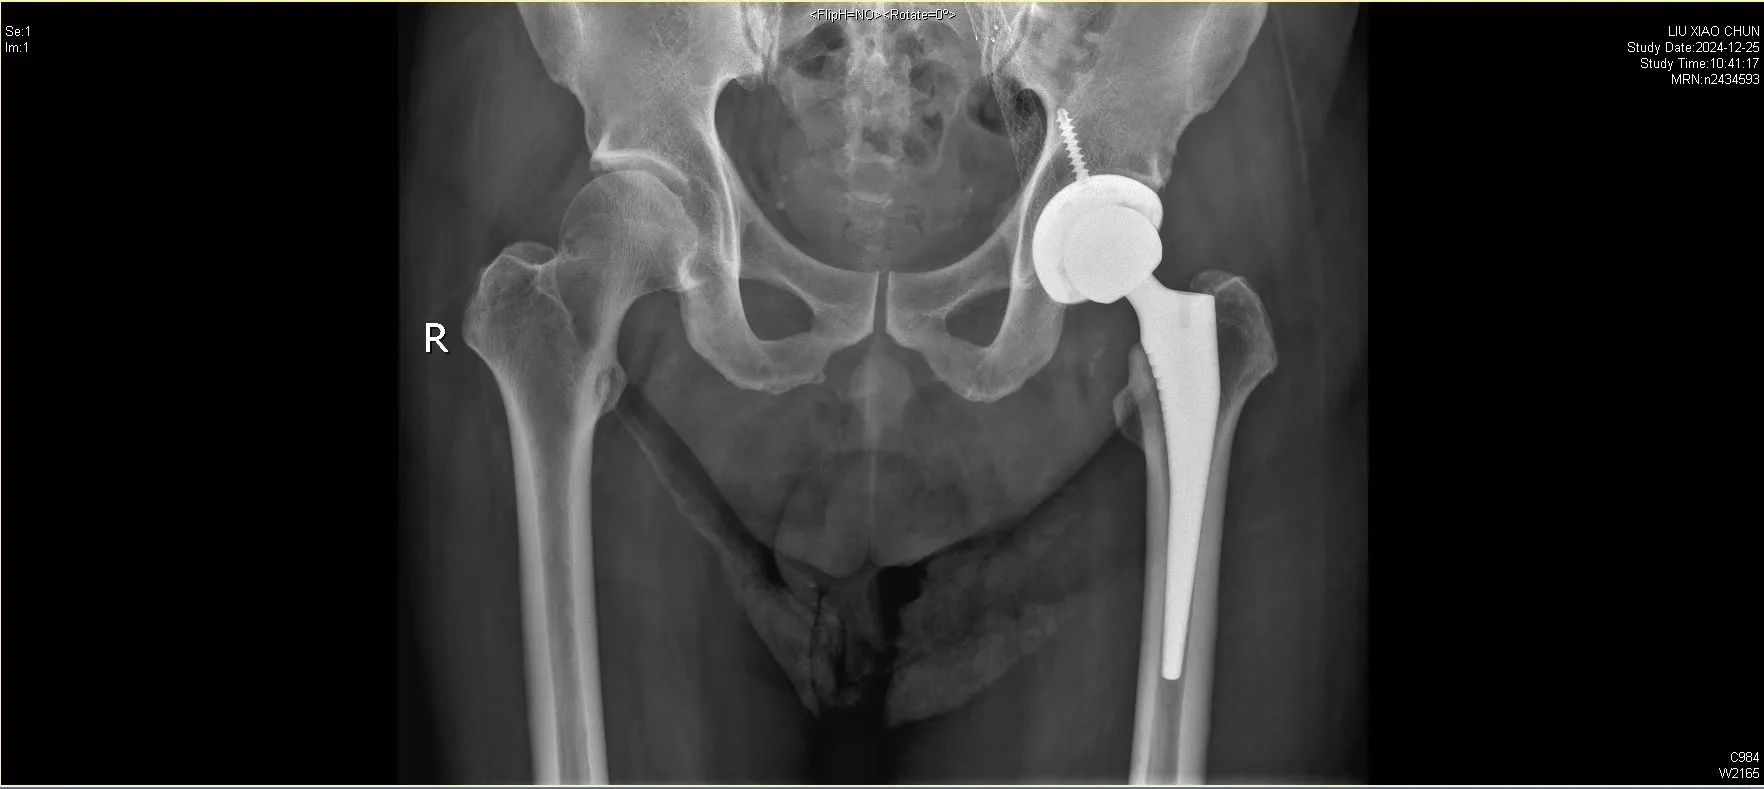

面对这位重度肝硬化合并多器官功能不全、髋部感染的患者,我院骨科与运动医学中心徐杰教授、邱美光主任及其团队成功为他实施关节置换手术。

患者刘先生患有酒精性肝硬化,并发脾功能亢进、血小板减少症、门静脉高压,以及肺动脉高压、慢性阻塞性肺疾病等多种严重基础疾病。同时,刘先生的髋部也遭受感染,患上感染性髋关节炎,还伴有左股骨头坏死。

在各学科专家的共同努力下,徐杰教授及邱美光主任的关节外科团队,经过细致的术前评估,为患者制定了周密的手术方案:1.先改善多器官功能及血小板功能;2.手术分期进行:一期处理髋部感染病灶、 切除坏死股骨头;二期成功实施髋关节置换术。

手术过程顺利,术中生命体征平稳,术后由多学科团队联合管理,康复团队为患者量身定制了个性化康复计划。在医护人员的精心照护下,患者恢复迅速,术后第二天即借助助行器成功下地行走。